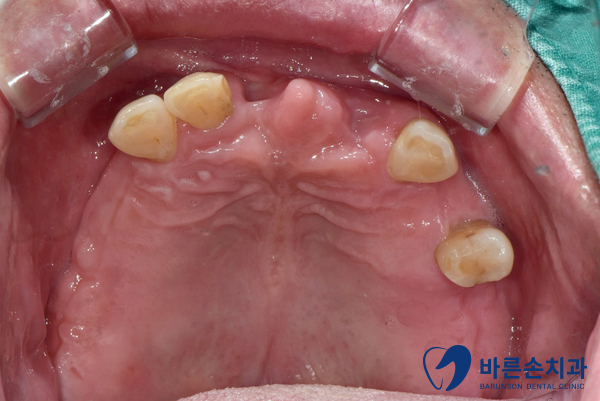

구강 내 확인을 해보니,

위 앞니를 포함한

다수 치아가 빠져 있는 상태로 내원하셨습니다.

위 앞니가 있던 자리가 이만 빠진게 아니라

이를 둘러싸고 있던 뼈 까지 다 녹아내린 상태입니다ㅠㅠ